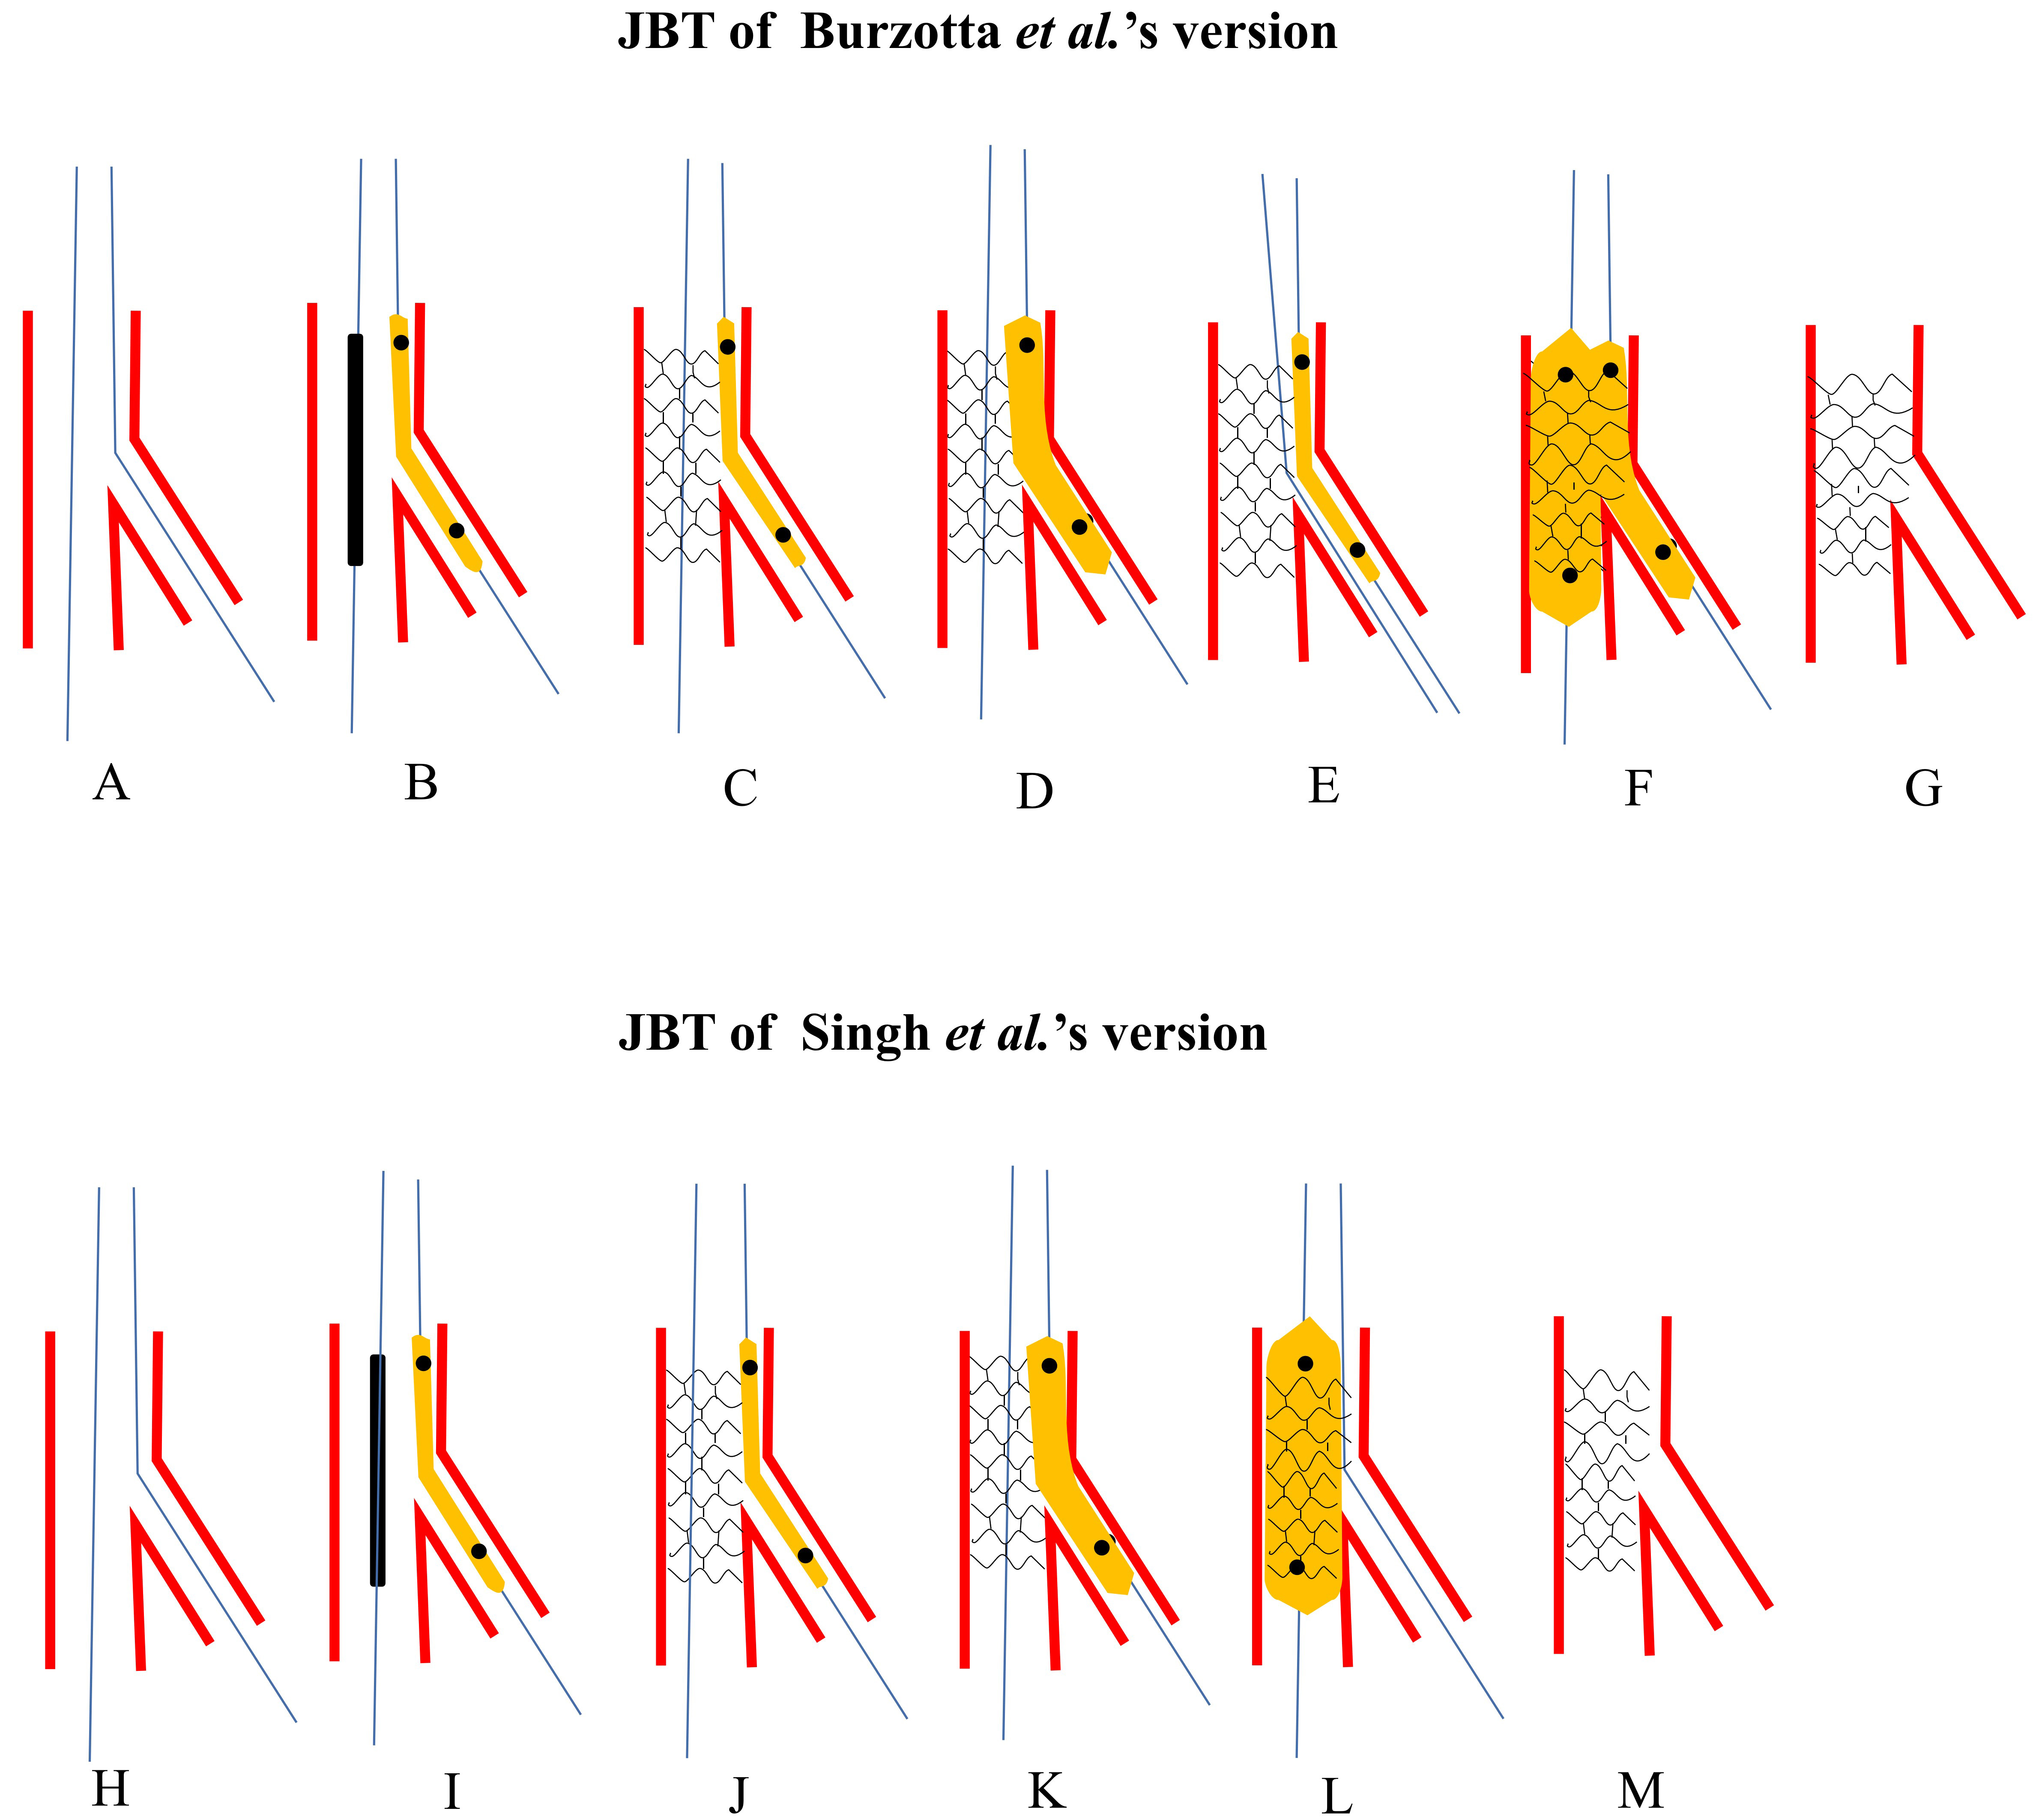

Unusual Evolution of Carotid Atherosclerosis in a Patient。Bilateral Large Vessel Occlusion Causing Massive Ischemic。701_2021_4754_Fig5_HTML.png。こちらの商品は裁断済商品になります。脳神経外科 脳血行再建の理論と実際。【タイトル】本書は「ENCYCLOPAEDIA of OCCLUSION」として知られ、咬合に関する包括的な情報を提供します。ピンズラーAmerican English Ⅰ。- タイトル: ENCYCLOPAEDIA of OCCLUSION- 出版社: The SHORIN Ltd.- 言語: 日本語- 状態: 経年劣化ありご覧いただきありがとうございます。Surgical occlusion of middle meningeal artery in treatment。購入後ScanすればiPadなどでいつでもどこでも読む事ができます。また再度メルカリに出品することができます。GPのためのアライナーシミュレーションガイド : これだけは覚えよう!歯科矯正…。歯科医学大事典 2巻~総索引。【出版社】この本はThe SHORIN Ltd.から出版されており、信頼性の高い資料です。【内容】咬合に関する詳細な知識を求める専門家や学生にとって、貴重なリソースとなるでしょう。カパンジー機能解剖学 II 下肢。メイトランド脊椎マニピュレーション。